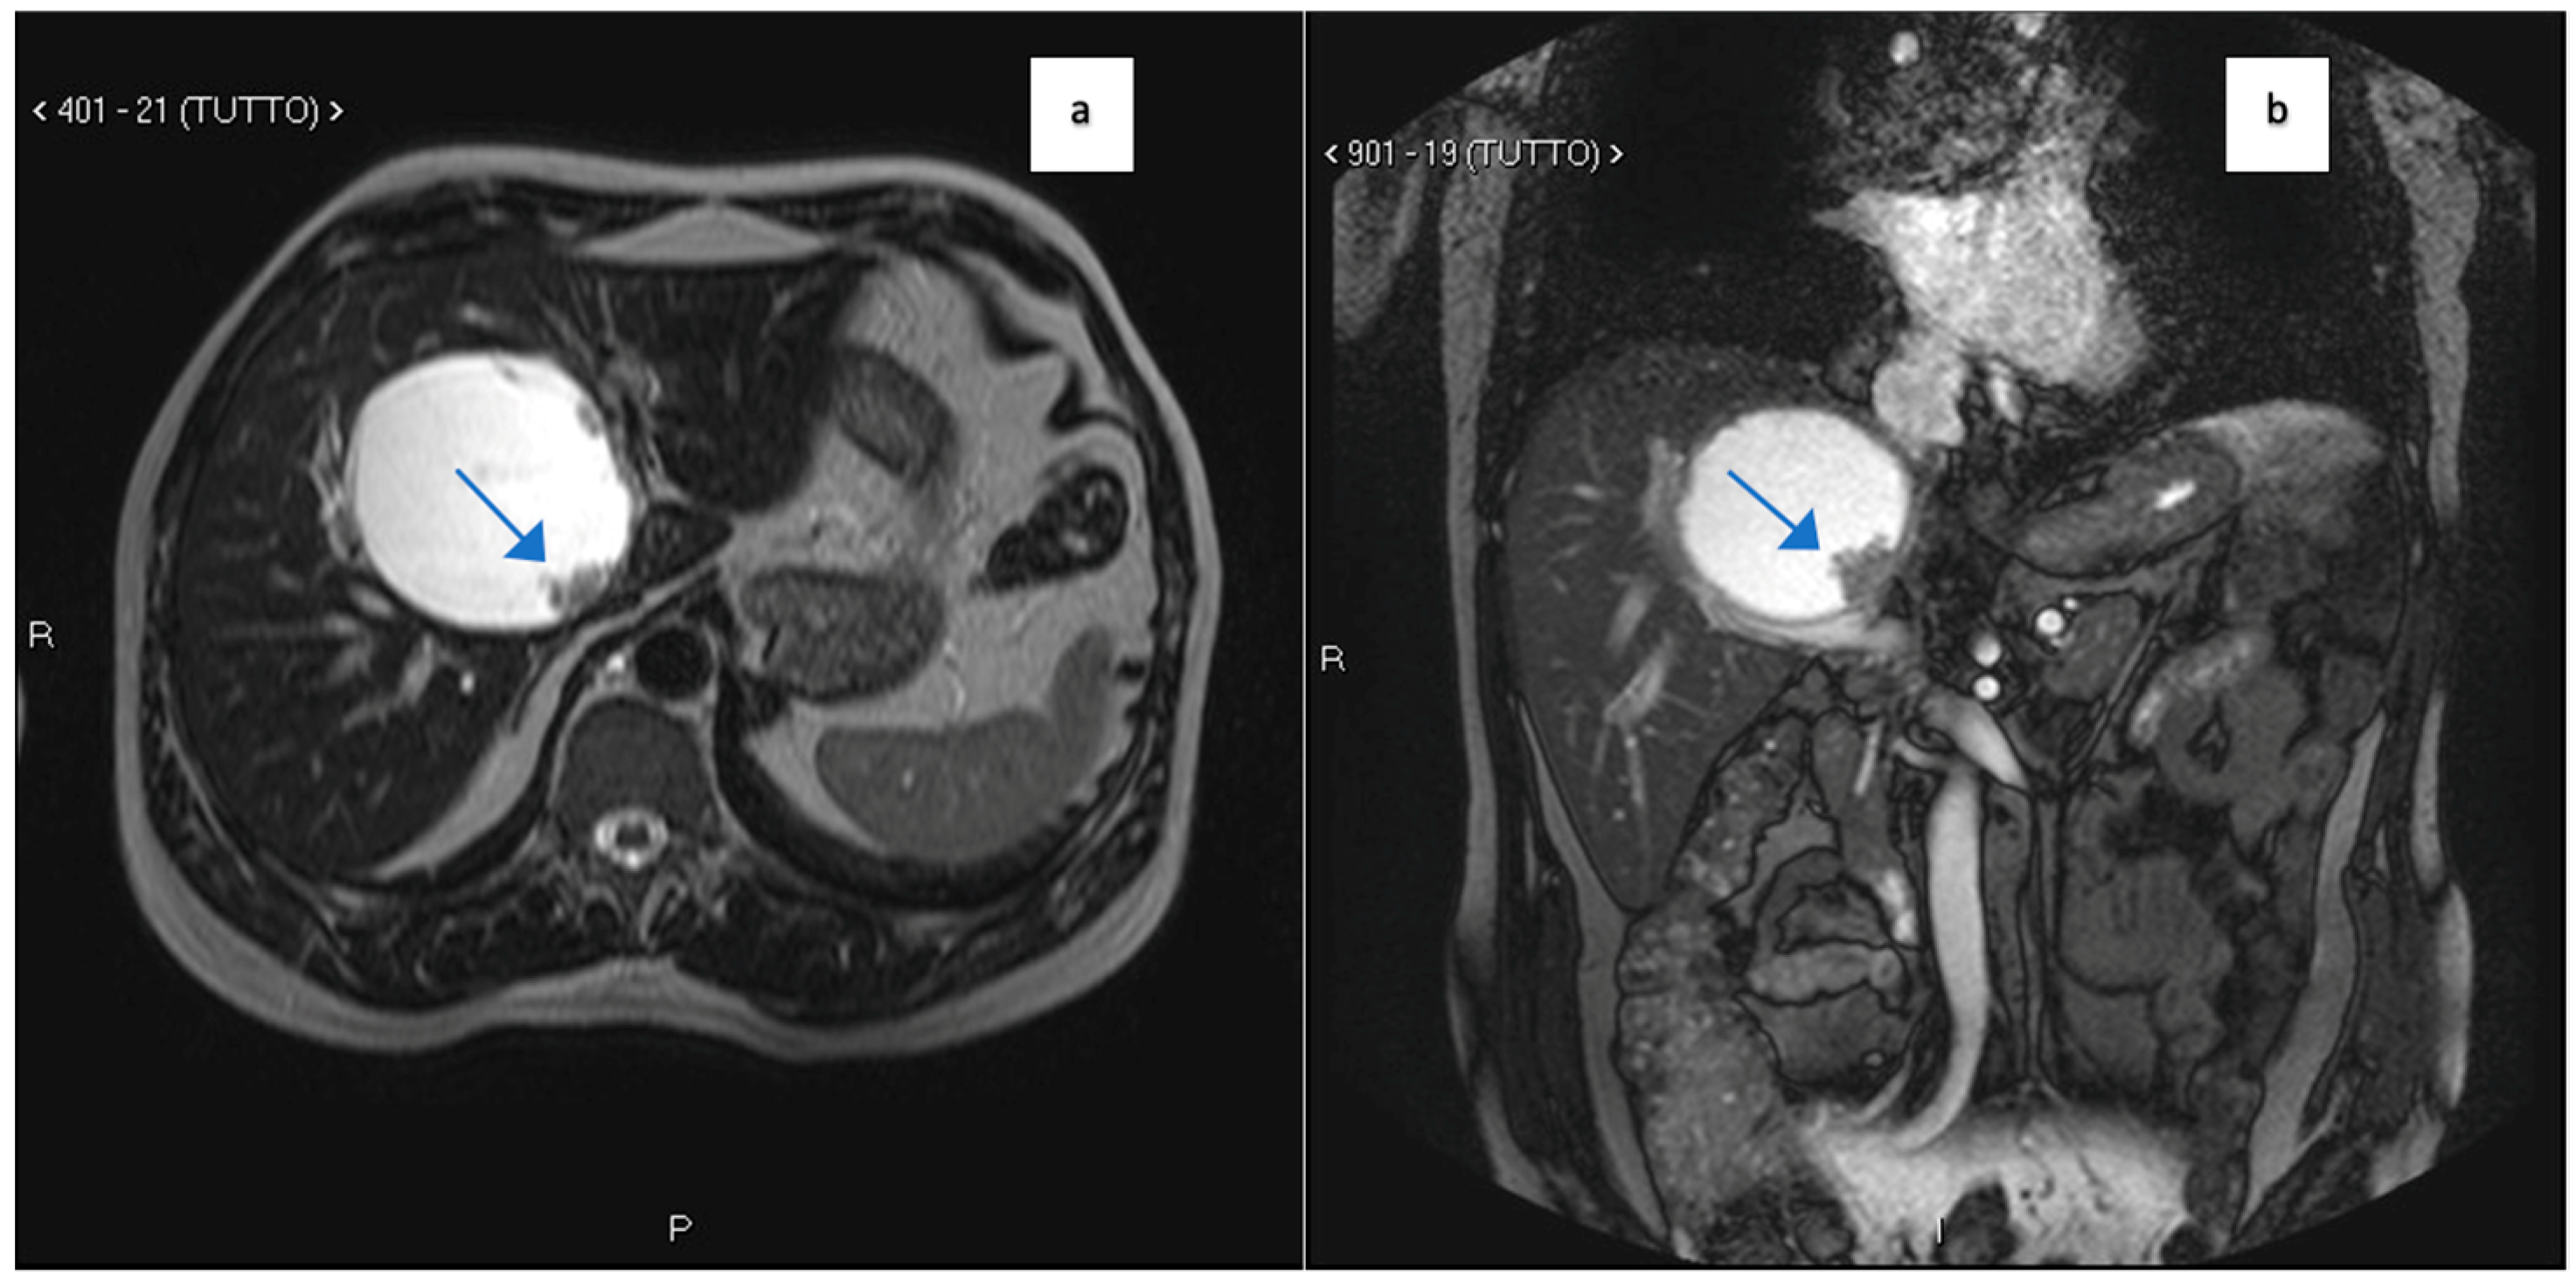

| Clinical Presentation | Incidental discovery of an 8 × 8 × 9 cm hepatic cyst | Presented with dyspnea, vomiting, jaundice, fever |

| Diagnostic Methods | MRI, MRCP, ERCP, histopathological examination | CT, MRI, laparoscopic liver biopsy, histopathological examination |

| Tumor Characteristics | Large cystic mass, thin walls, internal septa, papillary projections, enhancing solid components | Large lesion in left hepatic lobe, hyperintensity in T2-weighted images, restricted diffusion, contrast enhancement |

| Histopathological Findings | IPNB with foci of adenocarcinoma, oncocytic appearance, varying degrees of dysplasia, mucus within cyst | Adenocarcinoma with papillary clear cell and mucinous appearance, gland ectasis, cystic or pseudocystic aspects |

| Follow-up and Outcome | Initial recurrence-free survival for 8 years, recurrence treated with left hepatectomy, patient alive at 33 months post-second surgery | Disease progression despite aggressive management, patient died from hepatic failure |